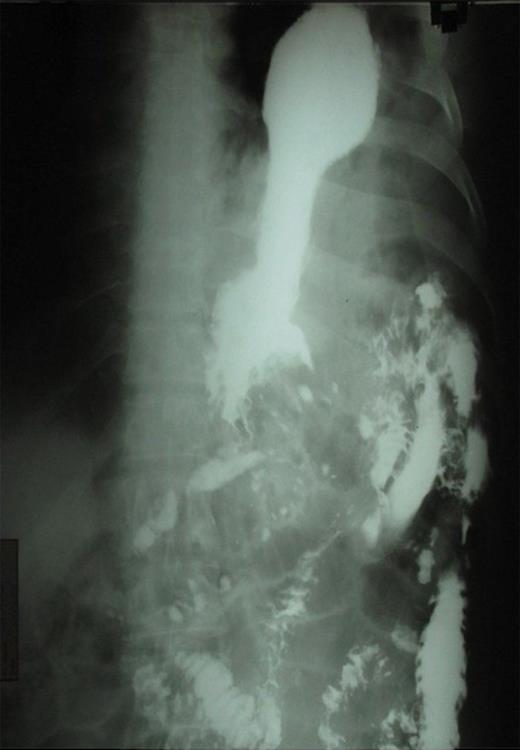

A 32 year old male was admitted to the emergency department with a history of nausea, vomiting, pain in the chest and upper abdomen as well as breathlessness of 3 days duration. He had a history of blunt trauma to the abdomen following a fall from a tree 4 years previously. He was then treated conservatively and no diaphragmatic hernia was detected. On physical examination the patient appeared pale, dehydrated and had dyspnea. Examination of the left chest showed decreased movement on respiration, absent breath sounds, bowel sounds were present and dullness on percussion. Apart from a mild anaemia (9gm/dl), all blood tests were within normal limits. The chest X-ray showed a large air-fluid level in the left thoracic cavity with a nasogastric tube within it, collapse of left lung field, obliteration of cardio-phrenic angle and shifting of the mediastinum toward the right side. (Figure 1)